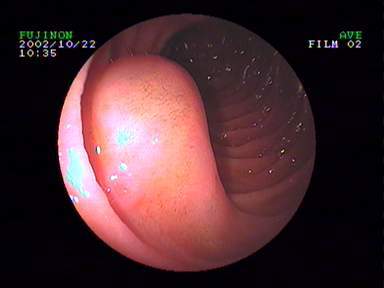

6.经口内镜下食管括约肌切开术(peroralendoscopicmyotomy,POEM)

POEM是治疗贲门失弛缓症的内镜新技术,基本取代传统的胸外科开胸食管肌切开术,成为首选的治疗方式。

贲门失弛缓症食管紧闭 食管粘膜切开建立隧道

食管肌切开 金属夹闭合切口